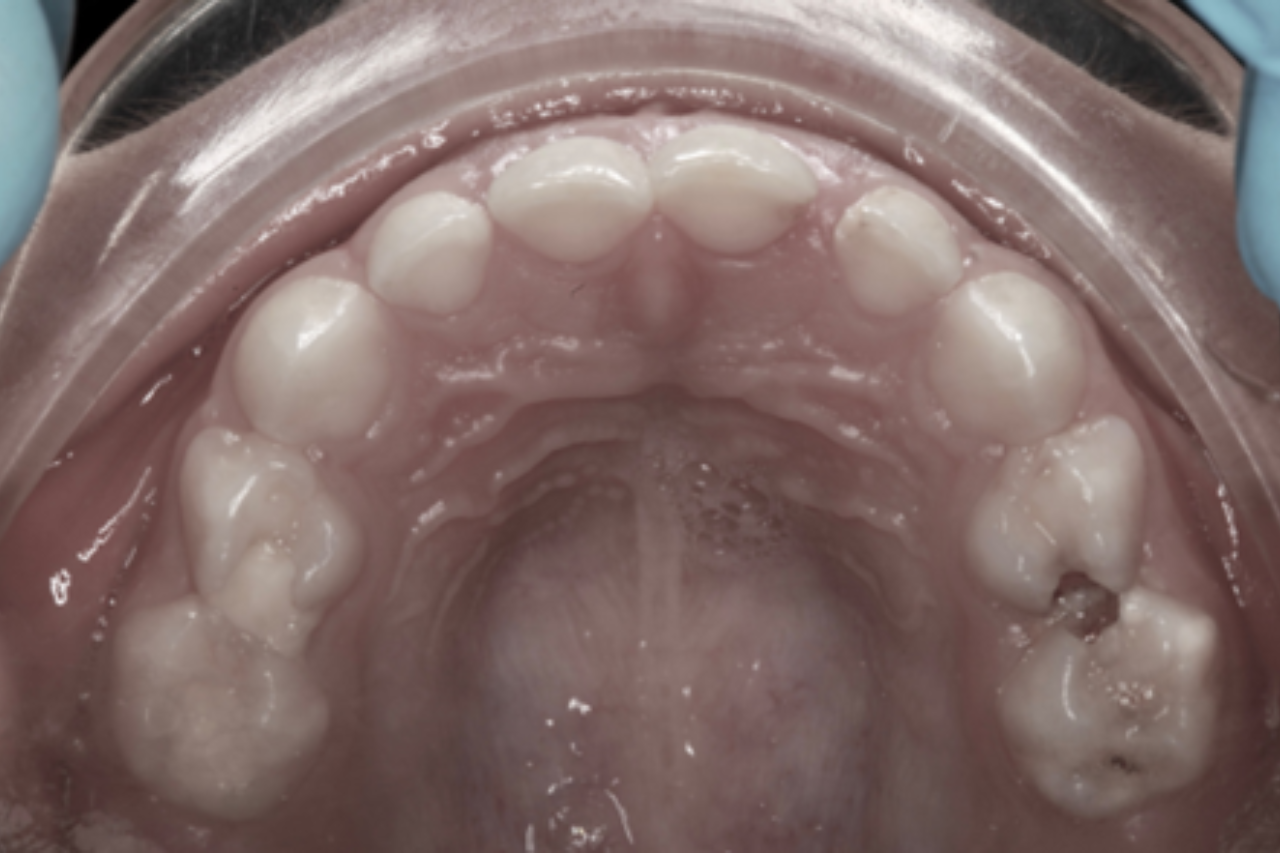

La paciente presentaba varias obturaciones (empastes) realizadas previamente en algunos molares temporales, muchas de las cuales no estaban adaptadas correctamente al contorno del diente o mantenían lesiones de caries por debajo. También presentaba lesiones de caries de gran tamaño sin tratar en dos molares superiores. Tras estudiar el caso con detenimiento, el plan de tratamiento restaurador propuesto fue el siguiente:

- Retirar las obturaciones que consideramos defectuosas y volver a realizarlas correctamente, limpiando la caries que presentaban por debajo, adaptando bien sus márgenes y dándoles una correcta anatomía

- Pulir y adaptar correctamente las obturaciones que consideramos que se podían mantener

- Tratar los dos molares superiores careados. Uno de ellos presentaba una caries que llegaba al nervio, por lo que tuvimos que restaurarlo mediante un tratamiento pulpar y una corona metálica.